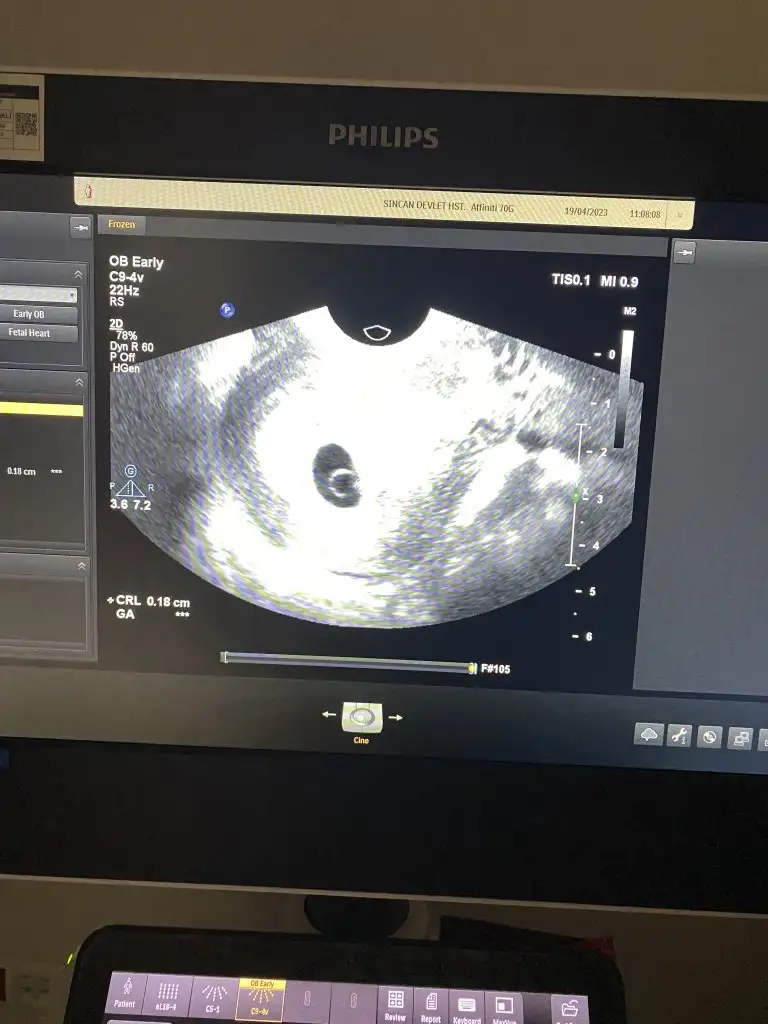

Kızlar merhaba kasım sonu aralık başı gözüküyor iki tarafıda takip ediyorum ramzi teorisine göre cinsiyet belli mi acaba tahminen vajinal ultrason 🫣

Eklentiler

• IMG_4674.webp

IMG_4674.webp

37 KB · Görüntüleme: 86